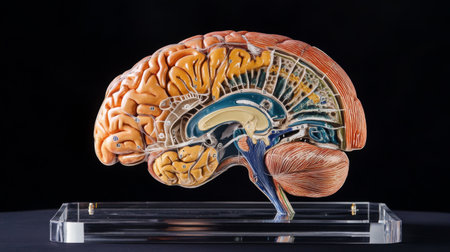

This detailed cross-section of the human brain illustrates its anatomical features, making it ideal for educational purposes in neuroscience and medicine.

This detailed model showcases human brain anatomy, perfect for educational purposes. Ideal for classrooms, medical training, and scientific research.